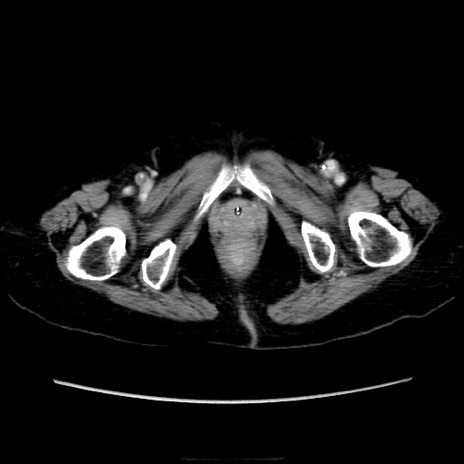

横断像